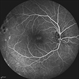

- Xlinked juvenile retinoschisis

- foveal schisis, spokewheel pattern

- Fundus photograph of a 27-year-old male with x-linked juvenile retinoschisis shows foveal retinoshisis with spokewheel pattern in his left eye.